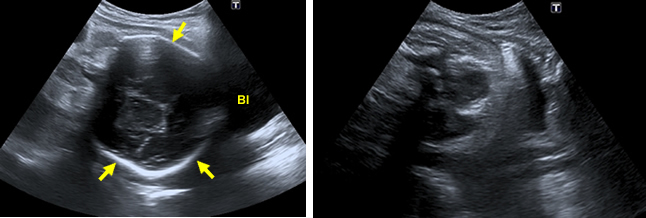

The lie or presentation of the baby is particularly important in late pregnancy, as the baby is less likely to change position. At this stage, certain critical features of the head and rump should allow you identify the presentation.

The fetal head is an oval structure. The bones of the skull produce bright echoes.

In the left image, you can see the bones of the skull of the fetus in the lower part of the uterus next to the bladder (bl). In the right image, the baby is in breech presentation. You can see the outline of the baby’s bottom next to the maternal bladder (bl).